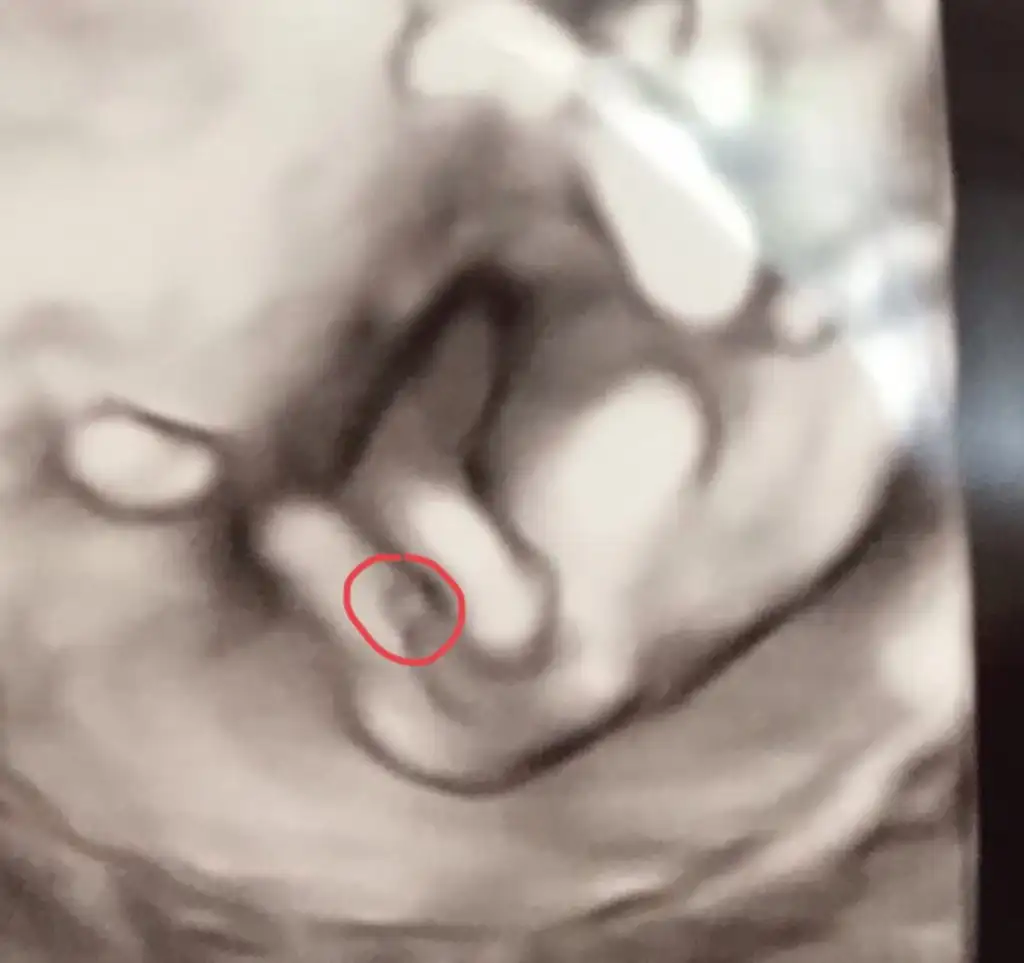

Hafif dönmüş göremiyorum başka usg varmıMerhabalar kızlar cinsiyeti sizce ne cok merak ediyorum 2 hafta sonra doktora gideceğim yorum yazarsaniz sevinirim![]()

Ya bana kız gibi geldi yine ama doktoru dinlemekte fayda var sonuçt erkek diye tahminde bulunan arkadaşlar da var o yüzden doktor erkek dediyse erkektir diyorum ilk miÇok sağolun allah herkese hayırlı evlatlar versin ama ben hala kız hissediyorum sizce doktorun kordonla felan karıştırma ihtimali var mı

Evet ilk doktor net gördüğünü söyledi ama ben kız olcağına çok inandırmıştım kendimi o yüzden kordonla mı karıştırdı diye aklıma takılıyor hepYa bana kız gibi geldi yine ama doktoru dinlemekte fayda var sonuçt erkek diye tahminde bulunan arkadaşlar da var o yüzden doktor erkek dediyse erkektir diyorum ilk mi